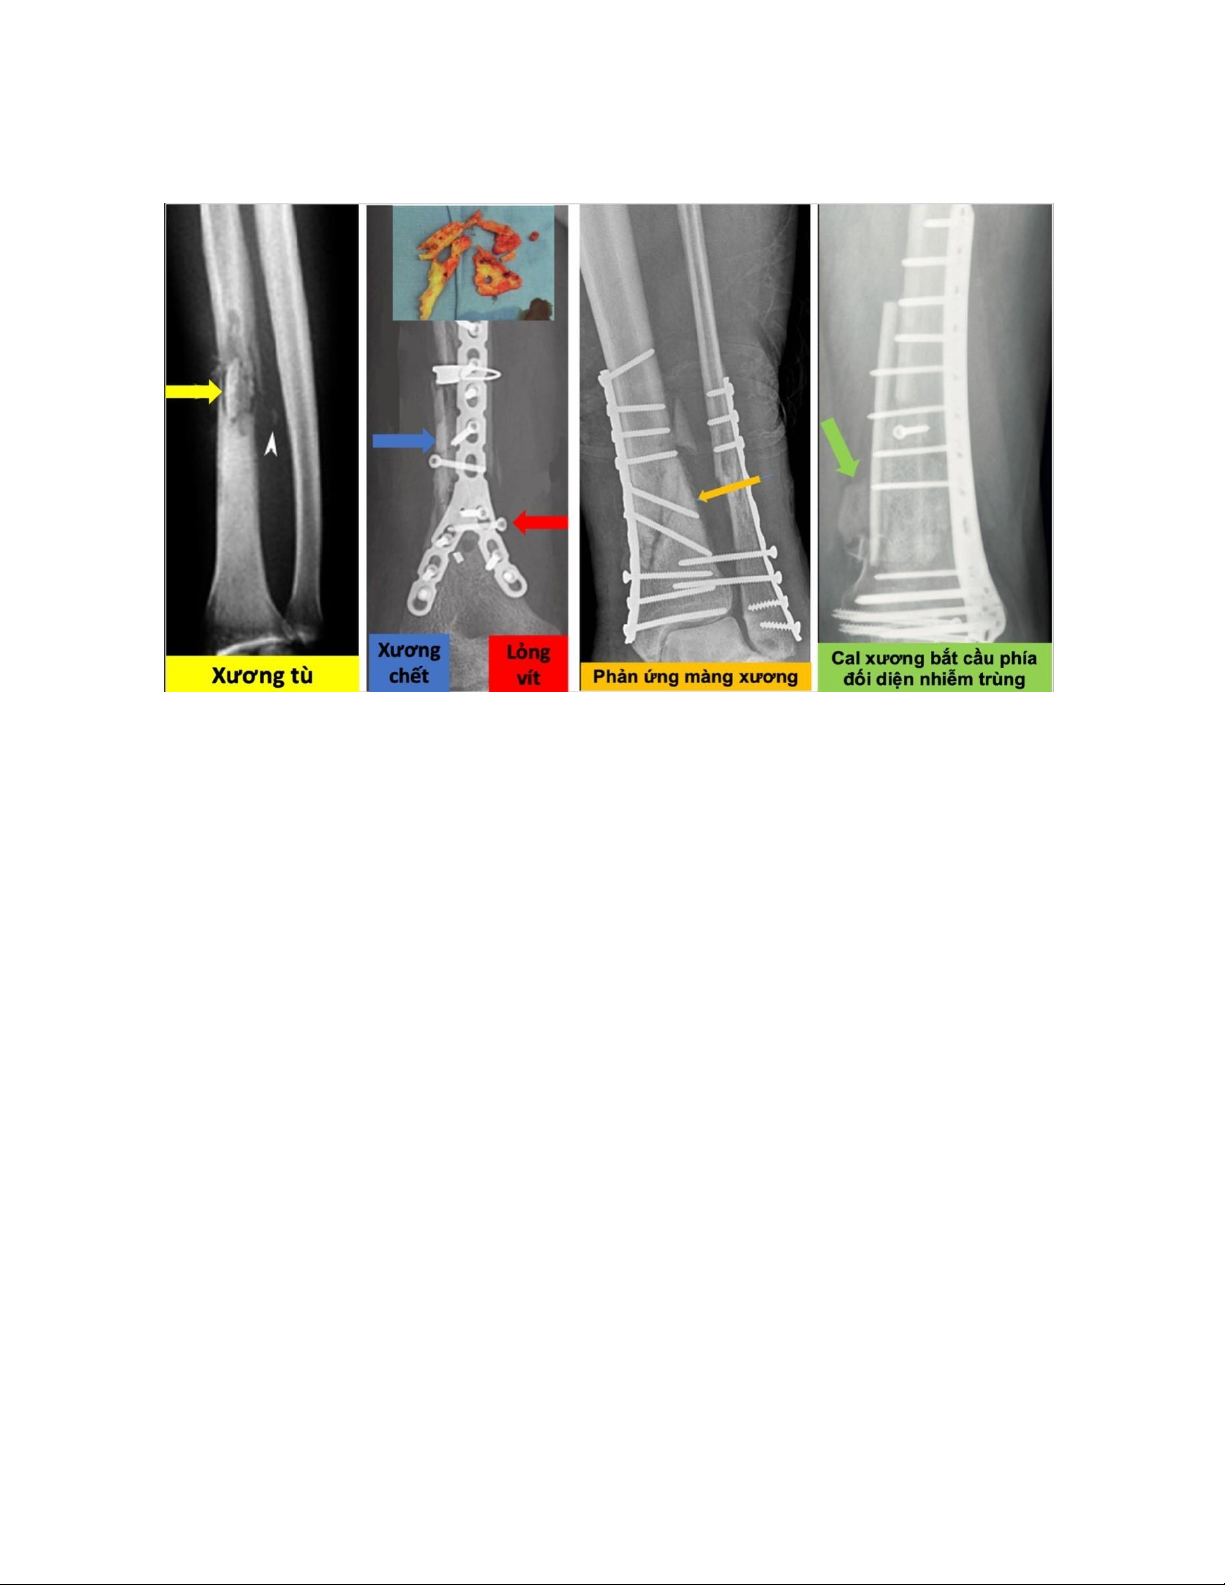

X quang quy ước: trong giai đoạn đầu của nhiễm trùng hầu như không

có sự thay đổi. Sau 3 đến 4 tuần thì bắt đầu xuất hiện các dấu hiệu như: phần mềm

sưng, khe gãy rộng ra do sự tiêu xương, lỏng vít. Sau đó là các dấu hiệu hủy xương,

xương chết, xương tù, phản ứng màng xương, đặc biệt là dấu hiệu cal xương bắc cầu

ở một bên xương và nhiễm trùng ở phía bên kia. -

Các d ấ u h iệ u nh i ễ m t r ù n g t r ê n X q u a n g 1.